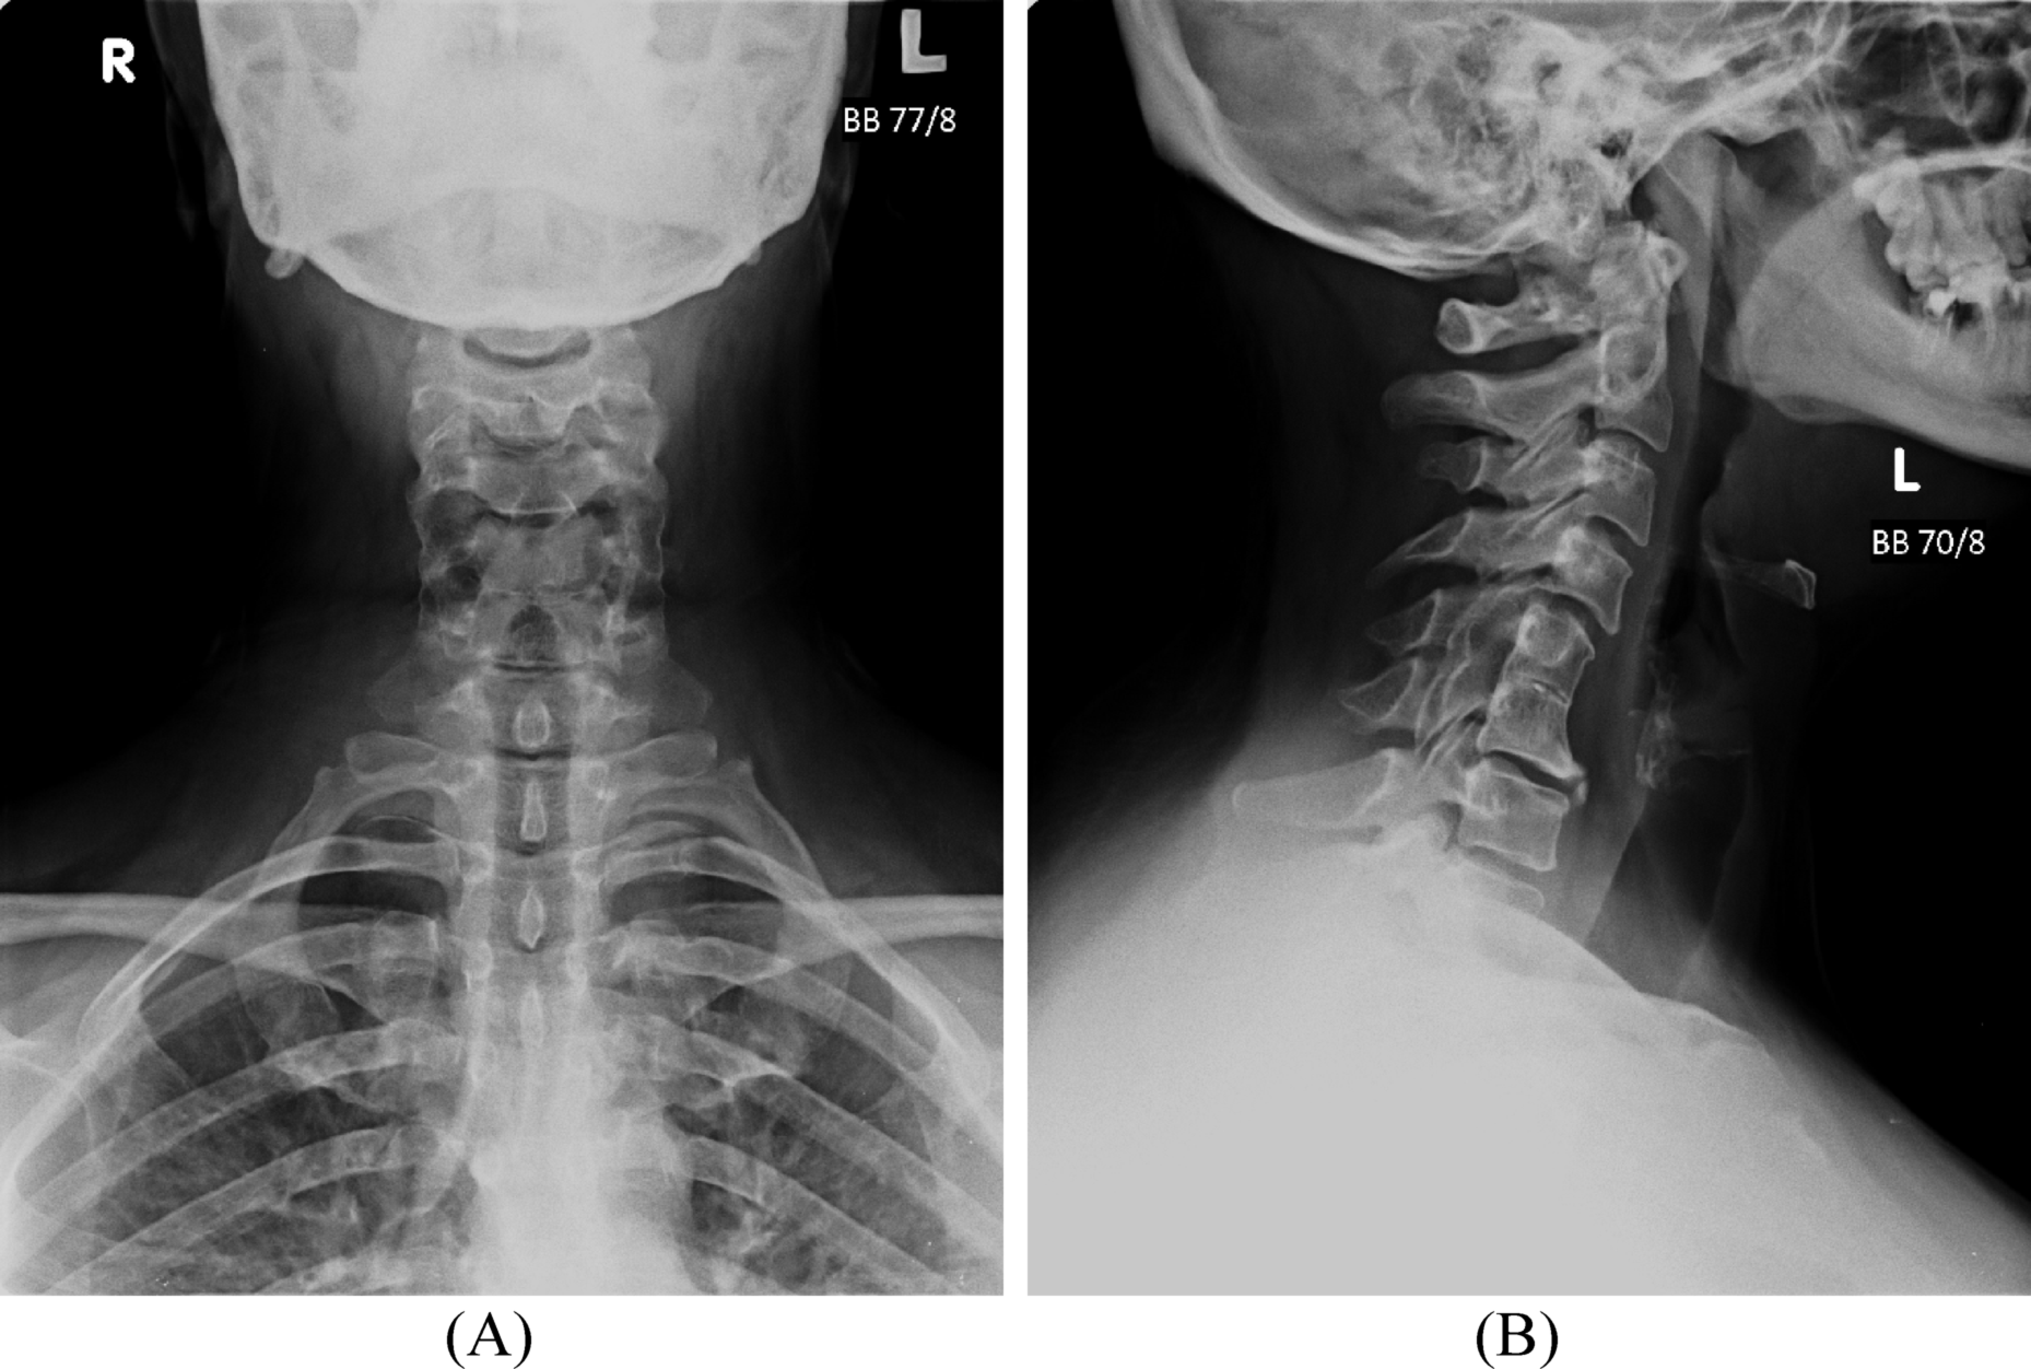

Radiographs of the hands, feet, and knees demonstrated mild degenerative changes, and cervical spine imaging revealed Klippel-Feil syndrome at the C5–C6 level, possibly contributing to the upper limb symptoms. Ultrasonography of affected joints did not reveal evidence of active synovitis. ENG was not performed due to limited availability but was recommended on an outpatient basis.

Fig. 1

A-B Anteroposterior (A) and lateral (B) radiographic views of the cervical spine demonstrating Klippel-Feil syndrome at the C5–C6 level, characterized by congenital fusion of the vertebral bodies with loss of normal intervertebral disc space and reduced cervical mobility